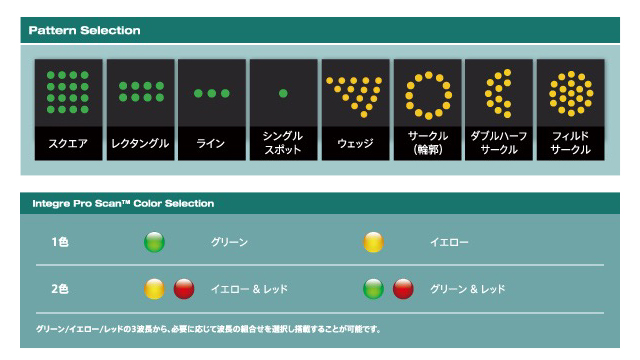

レーザー光凝固装置

インテグラプロスキャンレーザー光凝固装置

インテグラ プロスキャン レーザー光凝固装置は、エレックスが長年培ったSolid-State Laserの技術を更に進化させた“Zen Tec™”キャビティを搭載した、業界唯一の自社製レーザーキャビティ搭載のスキャンパターンレーザー光凝固装置です。